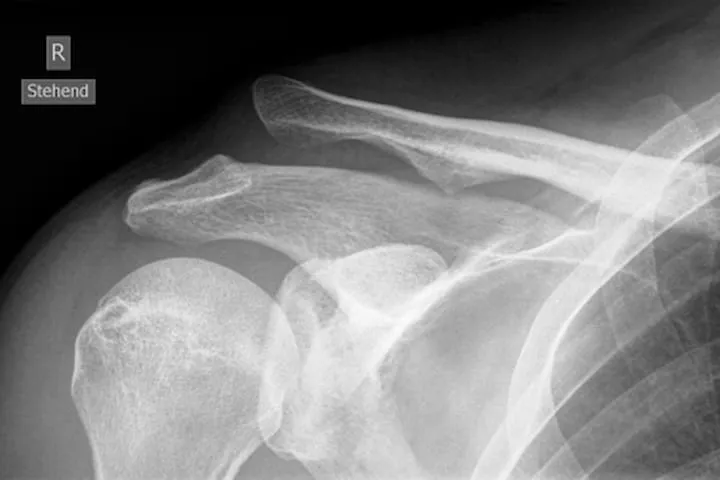

Röntgenfoto: er worden röntgenfoto’s gemaakt van de schouder. Hierop is te zien of het sleutelbeen uit de kom is en hoeveel speling er is. Bij twijfel kan een foto met gewichten in de handen (stress opname) de mate van AC-luxatie beter zichtbaar maken.

Een AC-luxatie is een ontwrichting van het gewricht tussen sleutelbeen (clavicula) en schouderdak (acromion). Dit letsel ontstaat typisch door een val op de schouder en veroorzaakt pijn en soms een zichtbare bult op de schouder. De diagnose is meestal klinisch duidelijk en kan bevestigd worden met een röntgenfoto. In de meeste gevallen hoeft een AC-luxatie niet geopereerd te worden en volstaat een behandeling met rust (mitella) en oefentherapie. Bij ernstige gevallen herstelt de schouder na een operatie ook goed. Met de juiste begeleiding en revalidatie krijgen de meeste patiënten hun schouderfunctie weer terug.